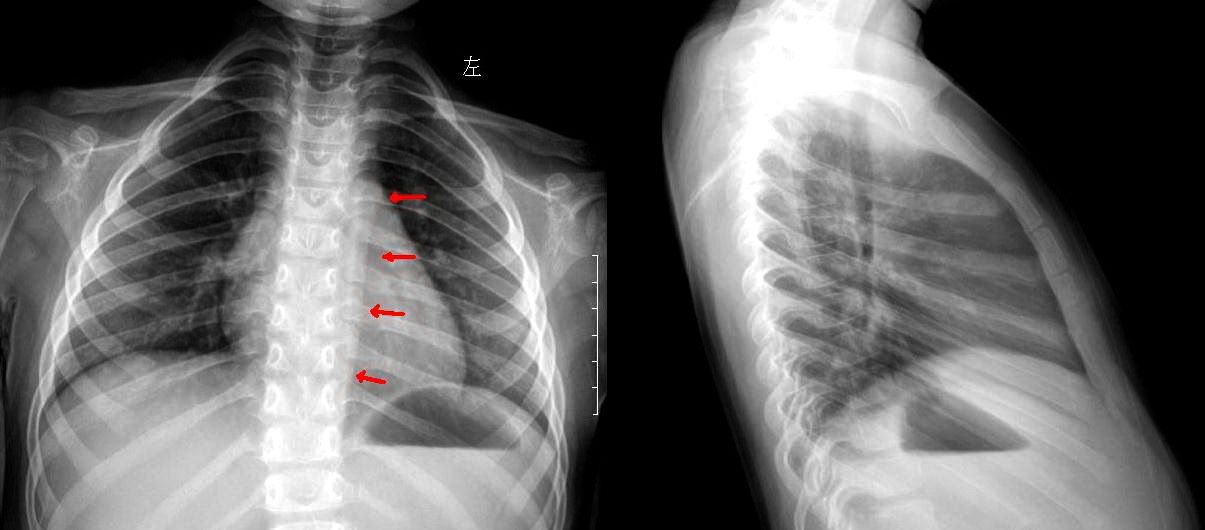

以下是引用shihai在2010-8-28 19:34:00的发言:[br]箭头所示为正常的降主动脉的左侧缘。椎旁线在其内侧,更靠近脊柱,未见增宽。

以下是引用sammycn在2010-8-28 20:14:00的发言:[br]可能系血管或后纵膈胸膜影。